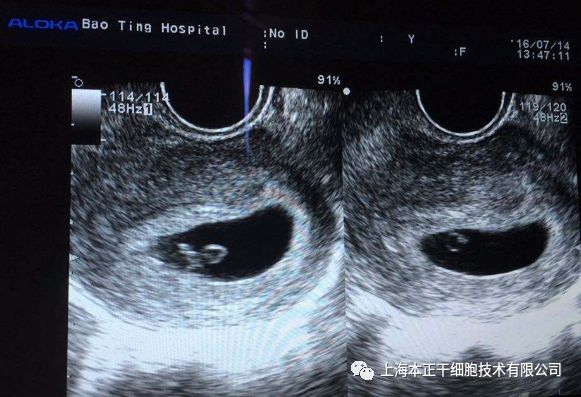

干细胞治疗方案:对患者刮宫后,在产生引导下用注射器经宫底及宫腔内注射入患者干细胞悬液,术后辅以阿司匹林和周期性激素治疗。超声检查结果显示患者术后子宫内膜再生较好,并且,患者通过体外受精(in vitro fertilization,IVF)成功怀孕,随访至妊娠第八周胎儿生长良好。

图5:胚胎移植后孕囊、卵黄囊、胚胎极及β-HCG阳性试验

图6:可见胚胎有心脏活动

图7:3D扫描8周的胎儿